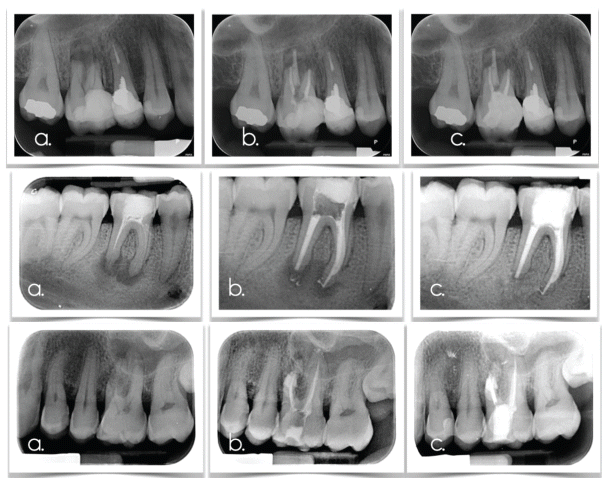

It is mainly caused by orthodontic treatment (3, 38, 46). If resorption is diagnosed during treatment, the magnitude of the applied forces is reduced, although this does not guarantee cessation of the resorption process; alternatively, orthodontic treatment is discontinued for approximately 3–6 months, allowing osteoclastic activity to subside (47, 48). If the diagnosis is made after completion of orthodontic treatment, regular follow-up and radiographic evaluation every 6–12 months are recommended (49) to confirm that resorption has not continued. Endodontic treatment is not required unless pulp necrosis occurs. Overall, the prognosis is excellent, especially when the resorption is small (<2 mm) (2, 33). (Figure 1)

It is caused by a microbial stimulus, namely, pulpal infection. The goal is to eliminate this microbial irritation. In permanent teeth with a closed apex, treatment includes endodontic therapy with chemomechanical preparation using sodium hypochlorite and EDTA, followed by placement of calcium hydroxide paste inside the canal for 2–3 weeks (14, 48, 50). Final root canal treatment is performed when radiographic signs of inflammation subside.

Therefore, the selection of the appropriate treatment must be based on differential diagnostic criteria that take into account: root maturity, pulp status, patient health and cooperation, and the clinician’s capabilities. In addition, several studies have examined pharmaceutical agents such as doxycycline, acetazolamide (58), ascorbic acid, and alendronate for the prevention or management of inflammatory resorption (59, 60, 61), but not for replacement resorption. Ledermix, which contains corticosteroids and antibiotics, has been shown to prevent inflammatory resorption, while Emdogain (62, 63) may contribute to periodontal healing, although its efficacy against ankylosis remains controversial. It should be noted that most of these studies involve replanted teeth and were conducted on animal models, limiting the generalizability of the results to humans (60, 62, 64). (Figures 2–4)

The term transient apical resorption also appears in the literature. This entity is observed in 23% of cases at 3 months and in 86% at 1 year after trauma. Radiographically, it appears as root shortening or blunting and is often misdiagnosed by clinicians as inflammatory resorption. In reality, it is an organismic healing process; therefore, periodic monitoring is recommended, especially if the patient exhibits no other symptoms. (Figure 5)